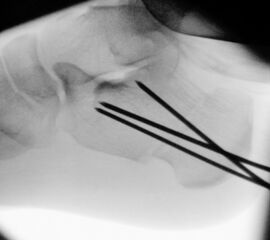

Zusätzlich schränken Wachstumsfugen die Wahl der Osteosynthese ein. Eine die Fuge kreuzende Osteosynthese ist ausschließlich mit Kirschner-Drähten möglich (Abb. 3).

Abb. 3 a-j: Beispiel einer Calcaneusverschiebeosteotomie mit offenen Wachstumsfugen und der entsprechenden Osteosynthese mit Kirschner Drähten. Lokalisation der Osteotomie (a), Lage der Fräse (b-d), Drahtlage mehrere Ansichten (e-h), Heilung der Osteotomie 4 Wochen postoperativ und Entfernung der Drähte (i-j).

Zum Lesen der Bildbeschreibung und zur Vollansicht bitte die Bilder anklicken. Bilder: A. Helmers.

Calcaneus-Osteotomie

Die minimalinvasive Calcaneusverschiebeosteotomie bietet eindeutige Vorteile gegenüber dem offenen Verfahren, sodass wir bei Kindern und Jugendlichen nahezu keine offene Verschiebeosteotomie mehr durchführen. Am Calcaneus liegt die offene Wachstumsfuge dorsal. Bei der Durchführung müssen Schenkel der V-förmigen Osteotomie daher etwas steiler angelegt werden, in einem stumpfen Winkel (siehe Abb. 3 a-j). Für die Osteotomie liegen unsere Patienten auf dem Rücken und der BV wird für die exakte Seitaufnahme eingestellt. Der Fuß lagert auf einem hohen OP-Kissen und die Osteotomie kann bequem mit einem langen Kirschner-Draht und einem sterilen Stift angezeichnet werden (Abb. 15).